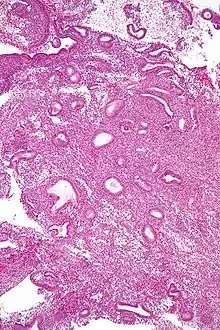

Biopsie endométriale révélant une hyperplasie simple.

L'hyperplasie endométriale est une prolifération bénigne de l'endomètre dans l'utérus. L'hyperplasie endométriale est classée en fonction de sa cytologie et du tissu glandulaire. Elle peut être simple, complexe et atypique, avec un risque croissant d'évolution vers un cancer de l'endomètre.